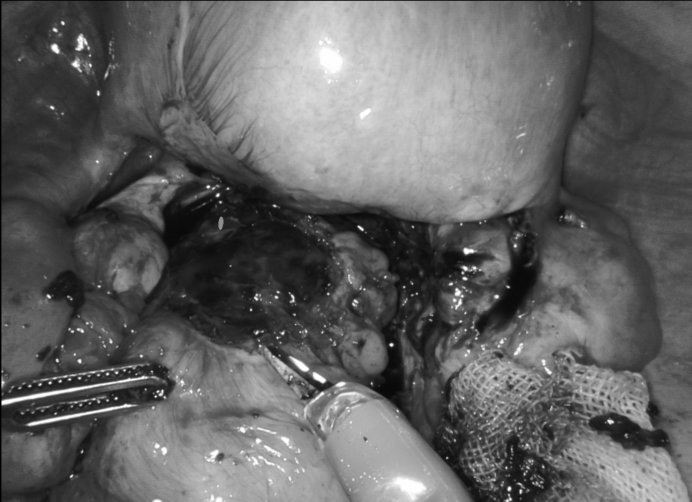

术中,范主任操控机械臂在腔内“转腕”,厚度误差控制在0.2mm以内,从直肠壁“片下”病灶,像剥生鸡蛋膜一样完整保留肠壁。最后,用可吸收缝线“编织”直肠壁缺损处,细致检查各处病损器官。全程出血仅10ml。

肠道异位病灶(左右滑动查看)

肠道异位病灶切除后(左右滑动查看)